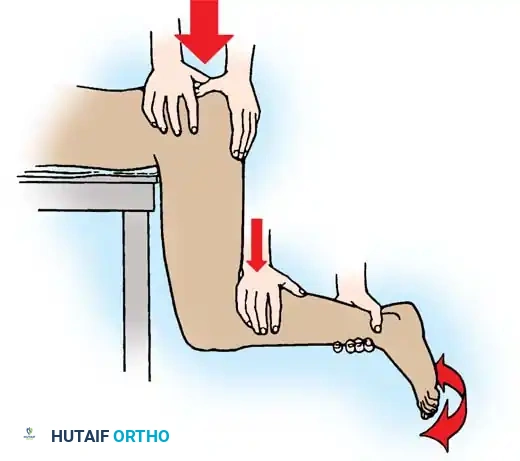

The Gravity Method of Stimson

The Stimson method is highly effective and minimally traumatic but requires the patient to be prone, which is often contraindicated in polytrauma patients with spine or thoracic injuries.

- The patient is placed prone on a stretcher with the affected lower extremity hanging off the edge.

- An assistant stabilizes the pelvis.

- The hip and knee are flexed to 90 degrees. The surgeon grasps the proximal calf and applies a steady, downward longitudinal force.

- Gentle rotation aids in guiding the head back into the acetabulum.

Fig. 52-47 Stimson maneuver for reduction of hip dislocation. The gravity-assisted downward force minimizes iatrogenic cartilage damage.